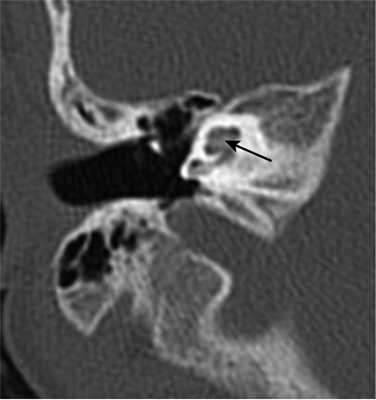

Рис.92 Адгезивный отит у больного, перенесшего баротравму.

С помощью КТ у пострадавших с баротравмой уха удается выявить следующие патологические изменения: разрывы цепи слуховых косточек, разрывы мышцы, напрягающей барабанную перепонку и спайки в полости среднего уха, как следствие баротравмы (рис.92).

Разрывы цепи слуховых косточек локализуются, как правило, в наковальне-молоточковом суставе, однако визуализация этой патологии на компьютерных томограммах все же не всегда возможна (лишь у 35% пострадавших).

Рис.93а КТ больного с разрывом цепи слуховых косточек: головка молоточка и тело наковальни визуализируются в гипотимпаническом пространстве.

Рис.936 КТ того же больного после оперативного вмешательства: наковальня удалена, тело молоточка находится около окна преддверия.

При обследовании пациентов с баротравмой следует помнить, что патологические изменения в барабанной полости могут быть небольшими, например, расхождение косточек при разрыве наковальне-стременного сочленениия. Вследствие небольшого смещения косточек это патологические изменения не видны на компьютерных томограммах, как из-за малой дистанции такого расхождения, так из-за небольших размеров самой наковальни, лежащих вне пределов разрешающей способности нашей КТ-установки.